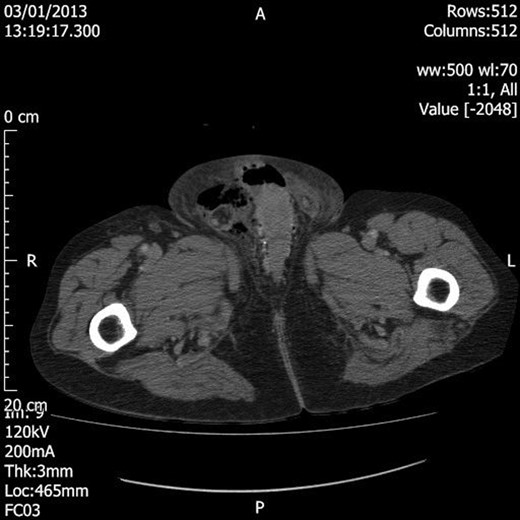

Blood tests showed grossly elevated white cell count and acute kidney injury, along with markedly deranged clotting parameters (Table 1). The patient was resuscitated with further intravenous fluids, and broad-spectrum antibiotics were commenced. Prothrombin complex concentrate was administered to correct the international normalized ratio. En route to theatre for surgical debridement the patient underwent computed tomography (CT) to assess for intra-abdominal sepsis, given the clinical findings of lower abdominal peritonism and the recent reported lower abdominal pain. This revealed a large amount of loculated gas mainly within the right hemiscrotum with superior extension into the inguinal canal, lower anterior abdominal wall and subcutaneous soft tissue, and lateral extension towards the right buttock; along the right lateral pelvic wall, there was a 10 × 4 × 6 cm collection containing fluid and air. No bowel loops were identified extending into the inguinal region (Figs 1 and 2).

Axial section CT image demonstrating loculated air within the right hemiscrotum.